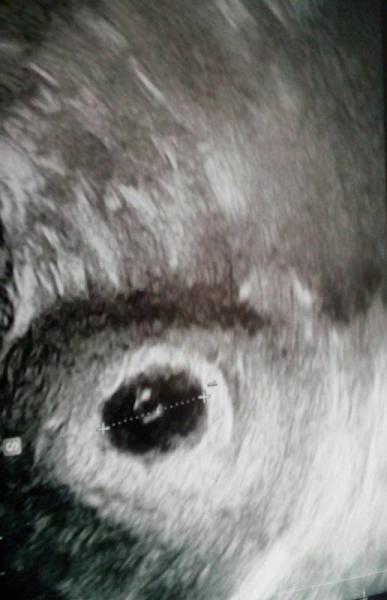

Heute bei 6+0 erster Ultraschall . Alles erstmal so wie es sein soll. Nächster Termin ist am 30.05. Da hoffen wir, dass man das -chen schlagen sieht.

Bild zu Auch vom Frauenarzt zurück - Forum für Januar - Mamis